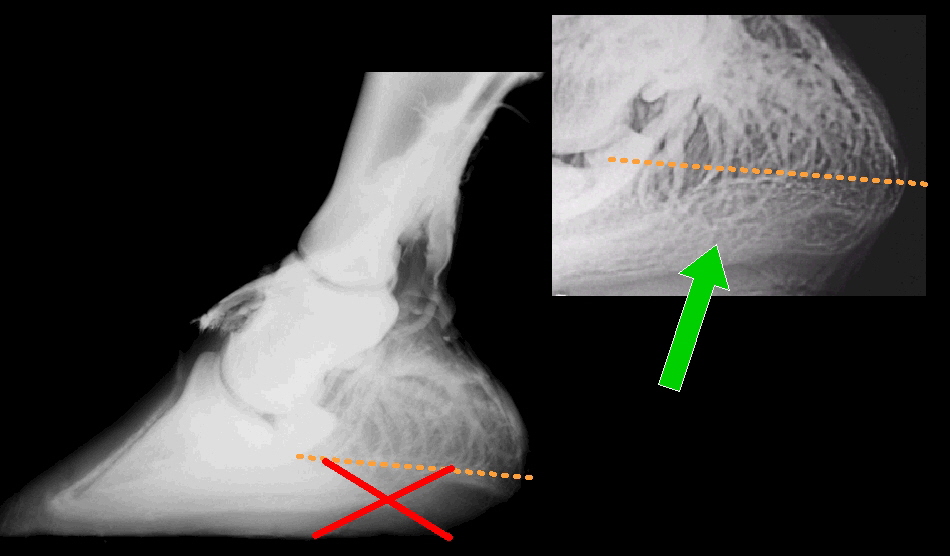

Nur ein korrekt geformter Huf mit gut ausgebildetem Strahlkissen und funktioneller Sohle kann als Stoßdämpfer fungieren, der die bei der Fußung auftretenden schädlichen Vibrationen effektiv wegdämpft und die Gliedmaße schützt. Ist der Huf vom Beschlag bzw. der Zurichtung her gut ausbalanciert, hat er eine enorme Adaptationsfähigkeit an die auftretenden Kräfte und bildet stabile Trachten, ein starkes Strahlkissen und einen tragfähigen Strahl. Fehlt mangels Bewegung oder wegen Behinderung des Hufmechanismus die Durchblutung oder ein gesunder Belastungsstimulus, kann der Huf nicht adaptieren. Bei dauerhafter Fehlbelastung bzw. fehlerhaftem Beschlag kann sich der Huf nicht anpassen sondern es kommt im Gegenteil zur Schädigung des Hufes. Die Dicke des Hufknorpels nimmt ab, das Gefäßsystem des Hufknorpels degeneriert und verliert seine hydraulische Dämpfungsfunktion, das Gewebe des Strahlkissens verliert seine feste Faserstruktur, die weitgehend durch Fett ersetzt wird. Das Strahlkissen wird weich und verliert dadurch seine Elastizität, seine Dämpfungsfunktion und Schutzfunktion für den Strahlbeinkomplex. Der “Stoßdämpfer” geht kaputt. Der Umbau äußert sich auch im äußerlich sichtbaren Trachtenzwang und der Atrophie (Verkümmerung) des Strahls. Umgekehrt zeigen Pferde mit gut ausgebildeten, gesunden Hufen wesentlich weniger Streßmerkmale an Hufbein, Strahlbein und den Weichteilstrukturen des Hufrollenkomplexes.

Der Dämpfungsmechanismus erfordert eine hohes Maß an Bewegung im hinteren Bereich des Hufes („Hufmechanismus“). Beim Auftreffen des Hufes auf den Boden bewegen sich die Trachten auseinander und das Hufbein sinkt in der Hornkapsel nach unten. Durch diese Bewegung im Rahmen des Hufmechanismus entsteht ein Unterdruck im Strahlkissen und im Moment des Auffußens wird Blut mit hohem Druck in das Gefäßsystem der Hufknorpel gepresst. Dies entspricht in seiner Wirkung der Funktion eines hydraulischen Stoßdämpfers. Die knöchernen Strukturen werden effektiv vor den extrem schädlichen Vibrationen geschützt, solange dieser Mechanismus nicht gestört ist. Die Weichteilstrukturen wie Sehnen und Bänder haben lediglich die Funktion einer Feder und sind an der Vibrationsdämpfung nicht beteiligt. Sie nehmen wie eine Feder lediglich die Energie auf, speichern sie und setzen sie beim Abfußen wieder frei.